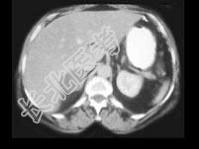

- 单项选择题女,45岁, 满月脸、向心性肥胖2年余,实验室检查: 血、尿皮质醇增高,结合CT图像, 最可能的诊断是 ( )

A、右肾上腺腺瘤

B、右肾上腺腺癌

C、右肾上腺转移癌

D、左肾上腺嗜铬细胞瘤

E、左肾上腺增生